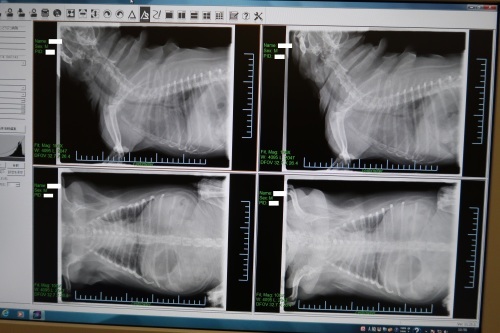

猫のレントゲン検査で何がわかる 獣医画像診断医が撮り方や安全性を解説 ペトコト

Web 犬の慢性気管支炎の診断は? 以下の3つを満たしていると慢性気管支炎と診断します 1年間に2ヵ月以上の連続した咳をしている 2ヵ月間のほとんどの日 粘液をたくさん出Web犬の気管と気管支の病気の気管支の病気 気管より奥にあるので、 その病気は触診等では分かりにくく、レントゲン検査や気管支鏡などの検査によって診断します。 気管支鏡は胃カメラのWeb 犬の気管支炎 レントゲン撮って見せてもらうと気管が白くなってる 気管支炎らしい ウイルスや細菌、アレルギーなど色々な原因がありなぜ急に気管支炎にかかったか詳し

Web シニアになると気管がよわくなります むせたり 咳したり レントゲンをとると、気管支の壁が白くうつります それを、石灰化といいますが、 原因は 加齢 慢性気管支炎Web 気管支炎の時のレントゲンの所見や診断! 影や白い部分についても レントゲン ツイート 気管支炎は、風邪やインフルエンザなどの後にかかりやすく、風邪や他の呼吸器